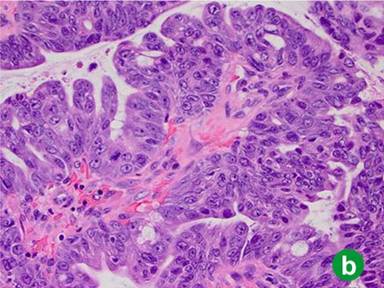

In 2011, four years after her original presentation, we performed a classic Whipple operation with a blood loss of 550 mL. Intraoperative frozen section of the common bile duct was negative for malignancy. The postoperative course was unremarkable and the patient was discharged to home 8 days later. Pathology report showed intraductal oncocytic papillary carcinoma 9 cm in greatest diameter, with 25 negative lymph nodes and microscopically negative surgical margins. The tumor showed diffuse high grade dysplasia and architectural complexity as well as mucin-containing intraepithelial lumina (Figure 2ab). The invasive component of the tumor was confined to the pancreas, moderately differentiated, measuring 1.9 cm in greatest diameter (Figure 2c). Additionally, a somatic KRAS mutation was identified at codon 12 and consisted of c.34G>A mutation. The case was discussed at Tumor Board and patient received adjuvant gemcitabine for six months. PET scan performed 16 months after Whipple operation showed no evidence of recurrent disease.

Figure 2. a. Low power image (20x) illustrates intraductal papillary growth pattern with oncocytic cells arranged in complex arborizing papillae. b. High power image (40x) showing distinctive mucin-containing intraepithelial lumina, imparting a cribriform architecture. c. Low power image (20x) displaying an invasive gland adjacent to the intraductal oncocytic papillary neoplasm. |

Intraductal oncocytic papillary neoplasm is considered the least common variant of IPMN. Histologically, it is characterized by an intraductal papillary growth pattern with exuberant, arborizing papillae, cribriforming and solid areas and oncocytic cells. One distinctive feature which is considered specific for intraductal oncocytic papillary neoplasm is the presence of mucin-containing intraepithelial lumina (Figure 2b). These tumors usually express MUC1 and MUC5AC, but MUC2 expression is weak or focal. Traditionally, intraductal oncocytic papillary neoplasms have been distinguished from IPMNs by lack of KRAS gene mutations; however, by itself this test is not reliable. As demonstrated in this case, up to 17% of intraductal oncocytic papillary neoplasms harbor a KRAS mutation [4].